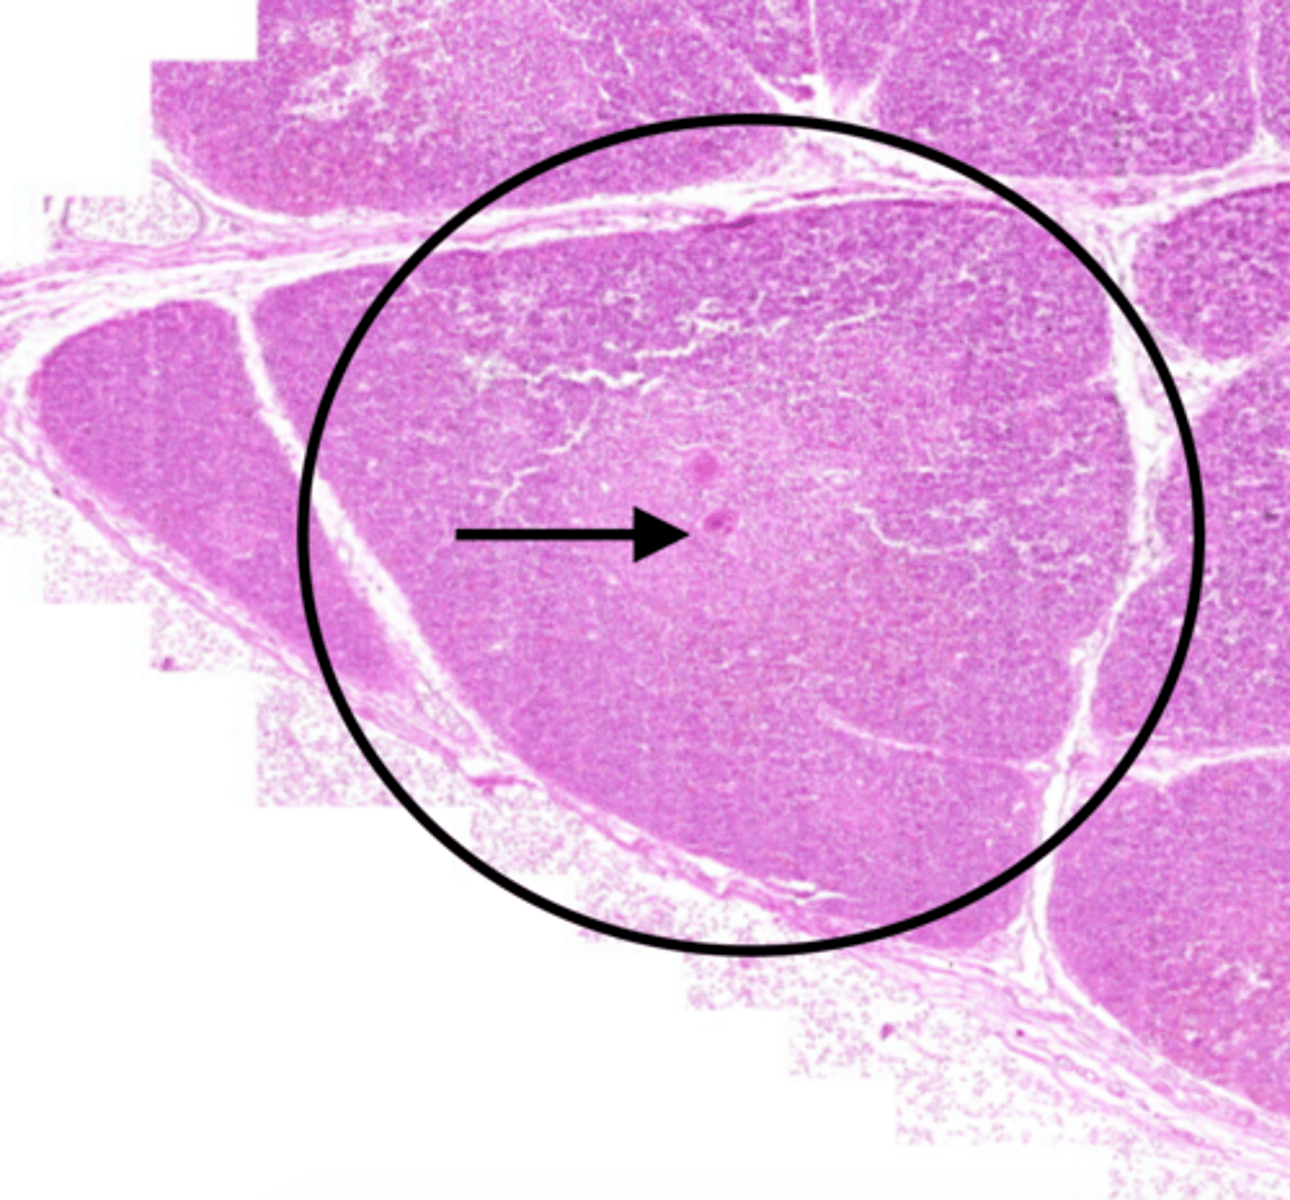

spleen

-the major function of this organ is to scrutinize the incoming blood for aged and malformed erythrocytes

-Will remove RBC and recycle their iron and begin disposal of bilirubin.

-On the lookout for any pathogens organisms or toxic materials in the blood.

red pulp (spleen)

-is the dark red tissue in the spleen containing sinusoidal capillaries, connective tissue fibers, and immune cells like macrophages, plasma cells, and lymphocytes.

-It destroys old red blood cells, removes pathogens and toxins

-facilitates lymphocyte movement between splenic tissue and blood.

white pulp (spleen)

has whitish appearance in a fresh spleen. Lymphocytes, macrophages surrounding small branches of splenic artery